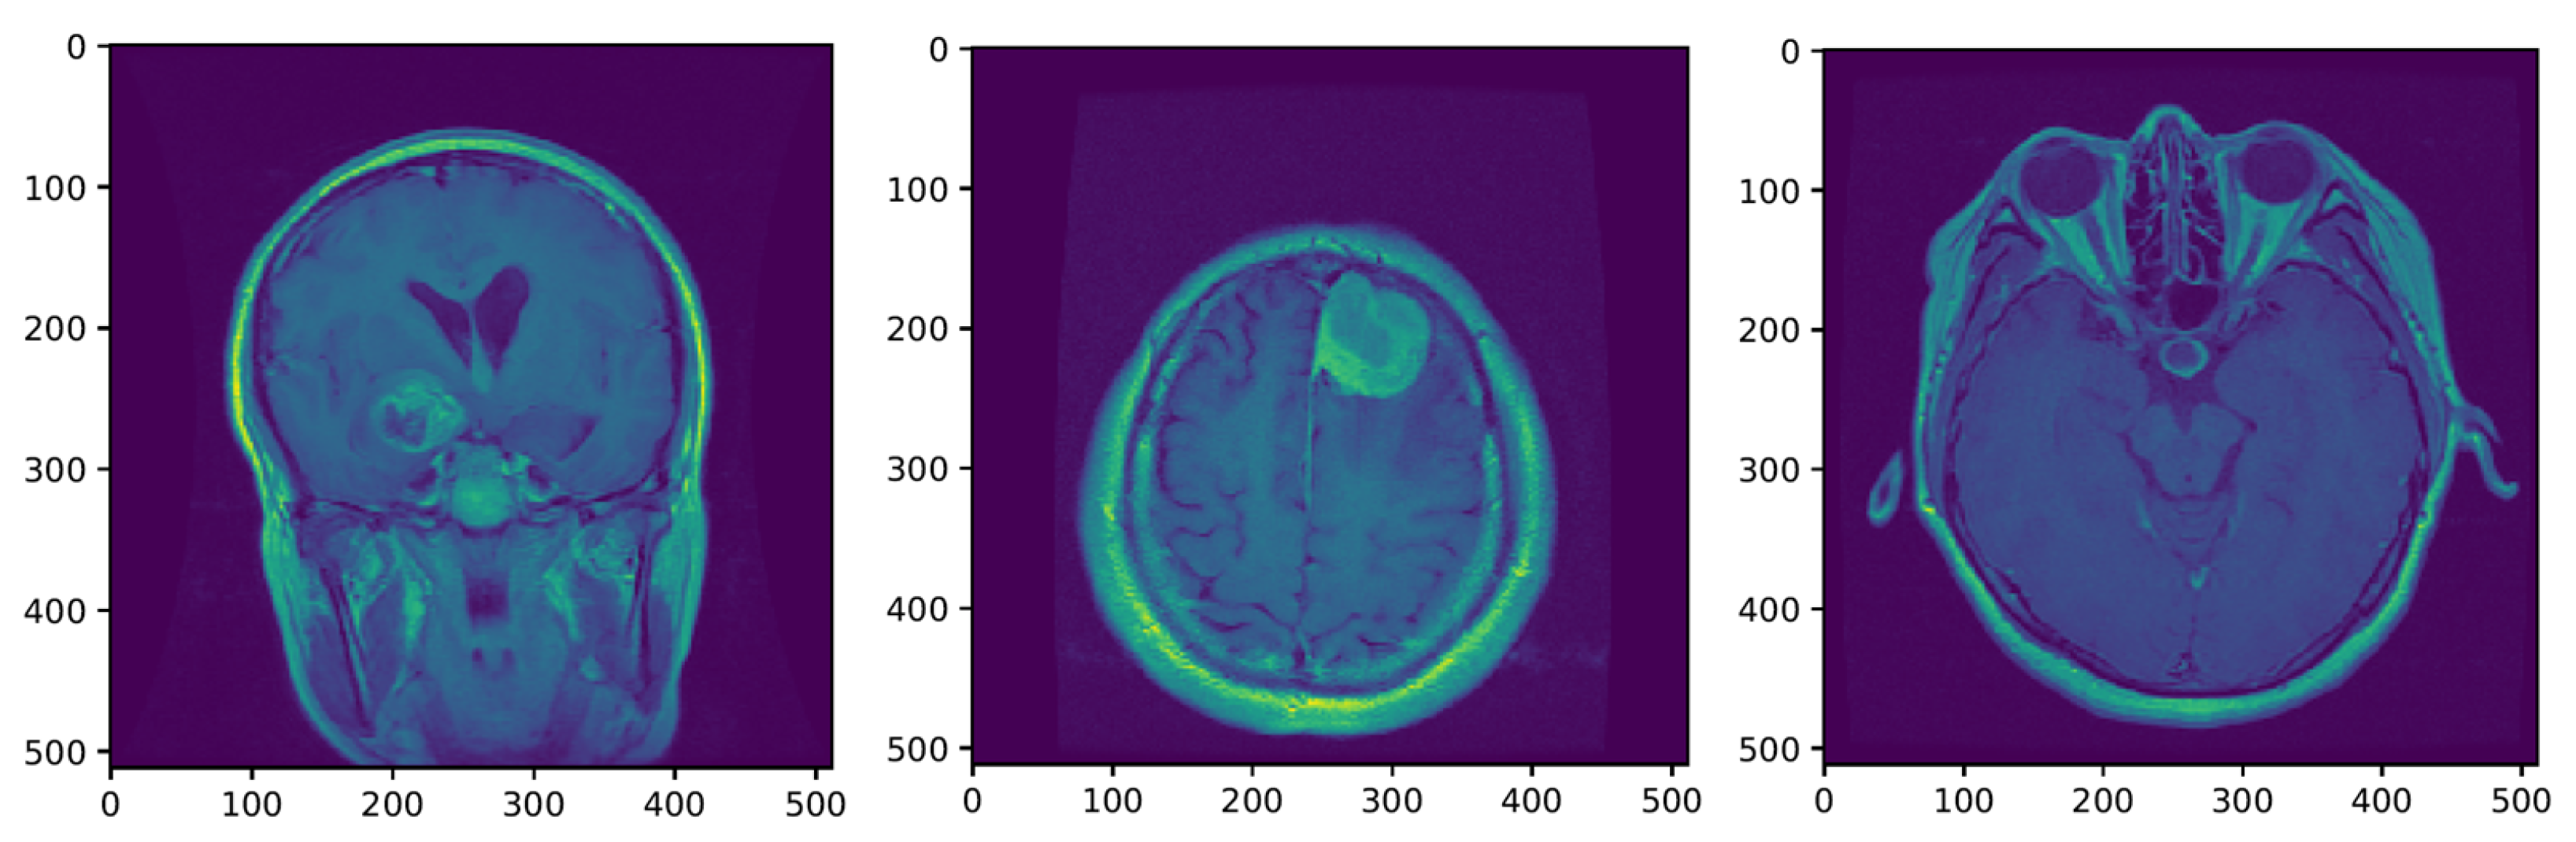

The MRI requires the setup of specific parameters, including radio-frequency pulse and gradient. T1 and T2 sequences are usually used in practice, with both providing specific information about the observed tissue. This research uses the T1 sequence. To reduce the amount of images required for the healthy brain, six sections were chosen from MRI images. A healthy brain sample is shown in Figure 3.

To help distinguish the tumor tissue and more precisely determine the tumor borders, the patients are typically injected with a contrast solution (Gadolinium). These images can be utilized in the classification of the tumor grade. Figure 4 shows axial MRIs with Gadolinium infusion of three grades of glioma brain tumors. Finally, Figure 5 shows three brain tumor cases from the second dataset utilized in this research [81]. As mentioned, all employed images were normalized to the [ 0 , 1 ] interval, and their dimension was set to 128 × 128 pixels.